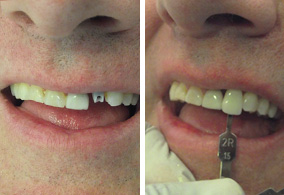

Es un procedimiento que permite recuperar las piezas faltantes en una sola sesión en la que se colocan los implantes dentales y se rehabilitan con sus prótesis, son muy pocos los casos en los que este procedimiento está indicado, una vez recibido este tratamiento es muy importante su cuidado post operatorio.

El Implante Dental se fusiona con el hueso de la mandíbula creando así un soporte estable para los dientes postizos, las prótesis, los puentes y las coronas individuales colocados sobre los implantes no se moverán dentro de la boca, proporcionando comodidad y seguridad a la hora de masticar y hablar.